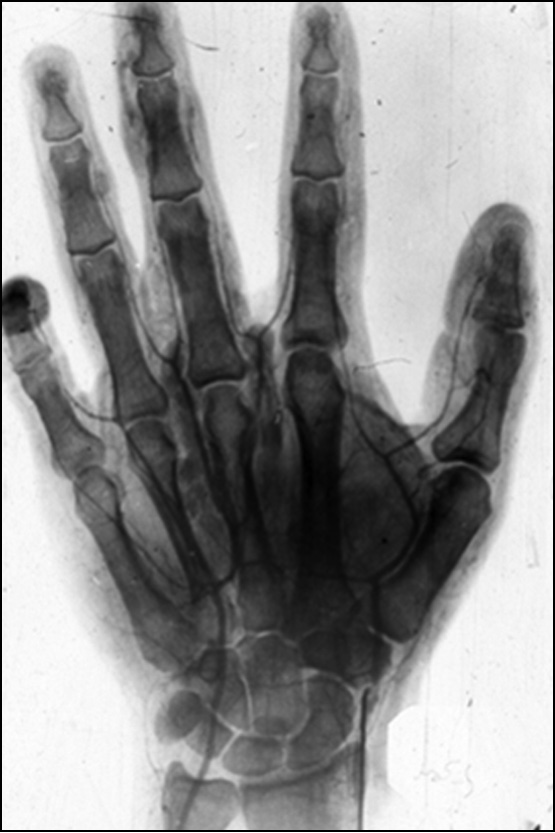

Для большинства ДОМТ кисти характерен медленный безболезненный рост. Основными признаками данной патологии являются наличие опухолевидного новообразования и связанной с ним деформации кисти или пальцев, ощущение неловкости и усталости в руке при работе, ограничение или нарушение функции кисти. Для гломангиом характерным симптомом является боль, которая провоцируется холодом, прикосновением или надавливанием на ногтевую пластинку. Боль может возникать и в результате давления опухоли на нервный ствол, носить иррадиирущий характер (в плечо и предплечье) и достигать большой интенсивности. Трофические нарушения особенно характерны при наличии опухоли из сосудистой ткани. Деформация и боль приводят к снижению функциональных возможностей кисти (рис. 1).

Рис. 1. Фибролипома срединного нерва и макродактилия II пальца.

Fig. 1. Fibrolipoma of the median nerve and macrodactyly of the second finger.

Истончение кожи встречалось при больших и длительно существующих доброкачественных синовиомах, неврилеммомах (рис. 3). При пальпации определялись консистенция образования, контуры, форма, величина, распространённость процесса, наличие болезненности, пульсации, отношение к подлежащим и близлежащим тканям (подвижность, спаянность), изменение местной температуры. ДОМТ кисти характеризовались ограниченностью узлов, чаще имеющих округлую или овальную форму, однородностью консистенции, подвижностью (рис. 4).

Рис. 4. Липома — широкая, «пухлая» кисть. Опухоль заполняет межпястные промежутки III и IV пястных костей.

Fig. 4. Lipoma of the hand, the wide, “plump” hand. The tumor fills the intermetacarpal spaces of the third and fourth metacarpal bones.